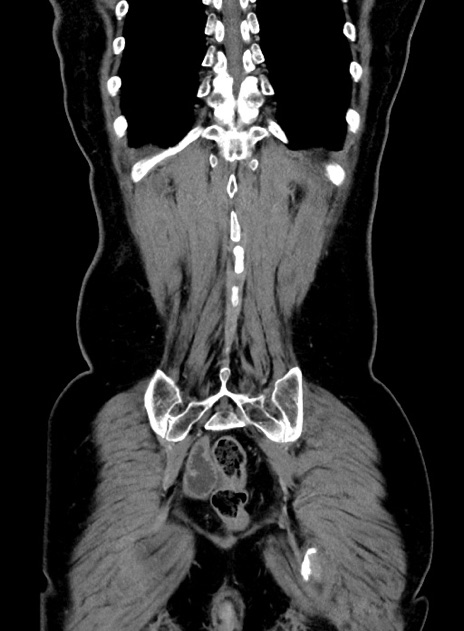

横断像

【症例】 60歳代女性

【主訴】むかつき、みぞおちの痛み

【現病歴】3日前よりむかつきがあり、食事がとれない。

【既往歴】糖尿病

【身体所見】発熱なし、心窩部圧痛軽度あるも、腹膜刺激症状なし。

【データ】WBC 7400、CRP 1.92